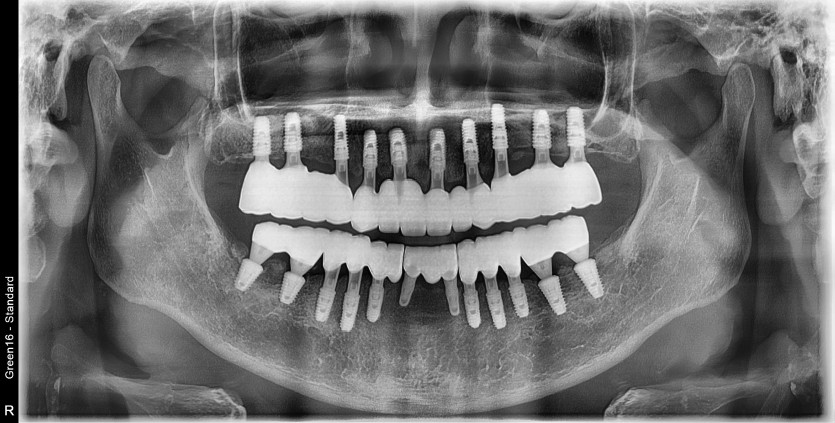

만 63세 전체 임플란트 증례(기존 임플란트 포함)

전체 임플란트 증례입니다.

(기존 임플란트 포함하여 교합 안정화)

16개의 임플란트로 완성하였습니다.